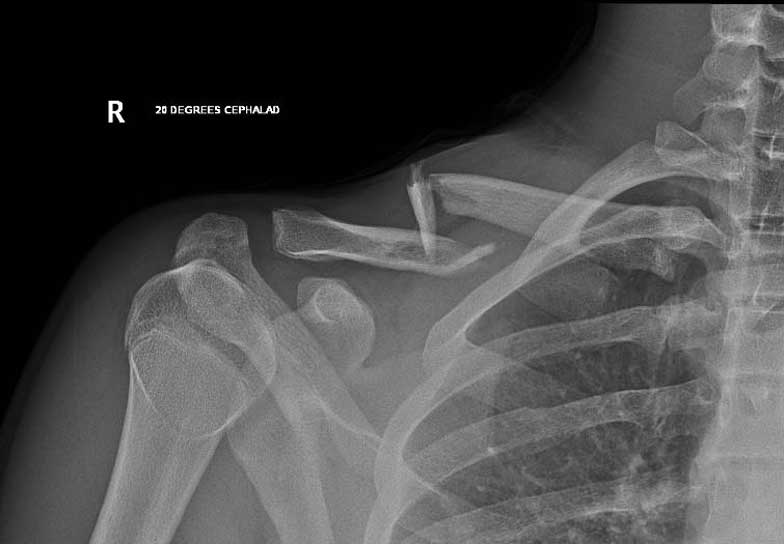

What do clavicle fractures look like on X-ray?

Below are examples of typical fractures that benefit from surgery.

2. Displaced Fractures

A fracture where the 2 bone ends are widely separated. These fractures have a higher incidence of not healing and if they do heal the bone is often deformed causing the shoulder to "not feel right".

A 15 year old female fell from her pushbike causing a displaced left mid-shaft clavicular fracture. Seen 5 days later, plate & screws inserted 2 days later.

Image

DIsplaced fracture before surgery